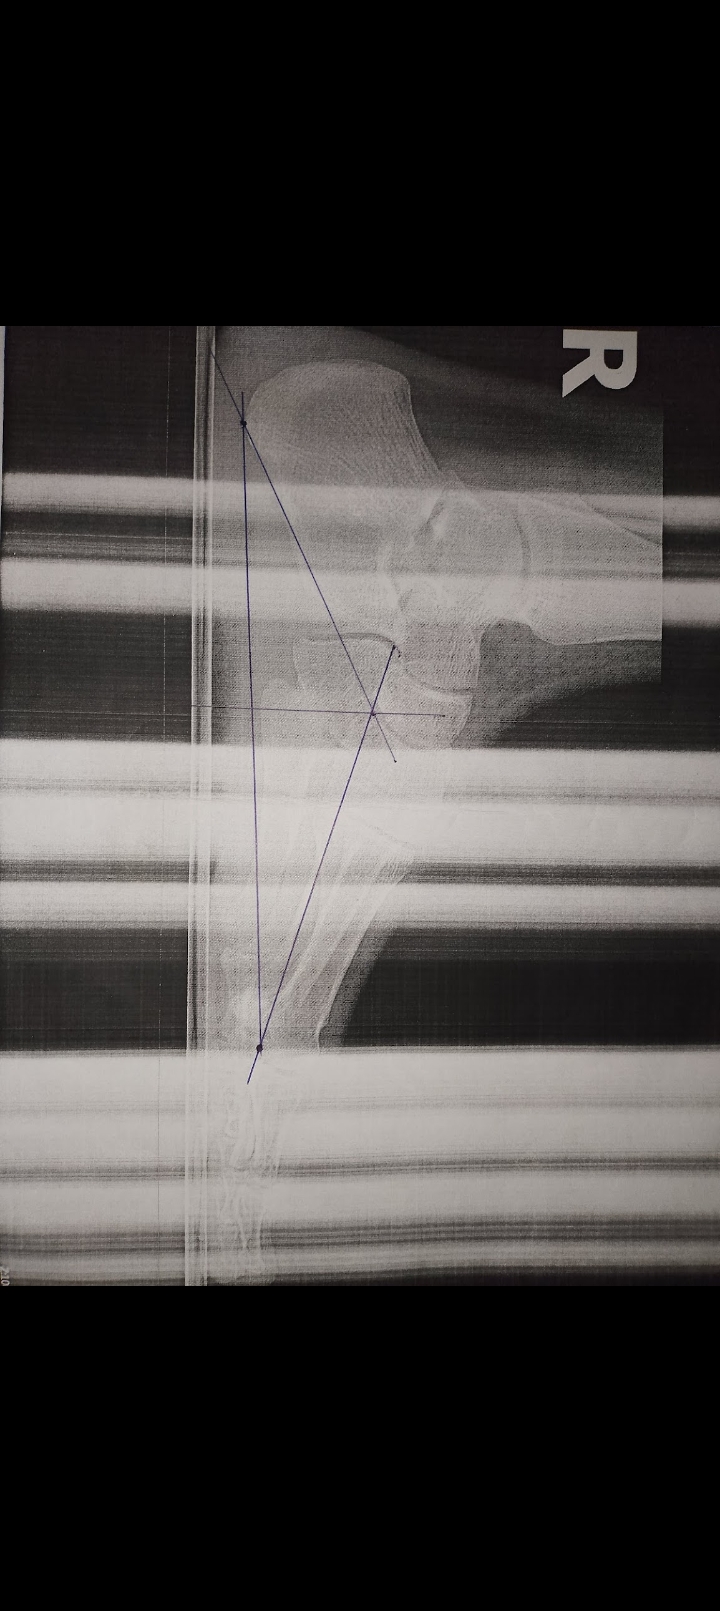

Are my growth plates open or closed? (Sorry for the bad picture) I'm 17 years old, 173cm tall, haven't grown a centimeter since I was 14, help

• Screenshot_20260105-232139.jpg

Screenshot_20260105-232139.jpg